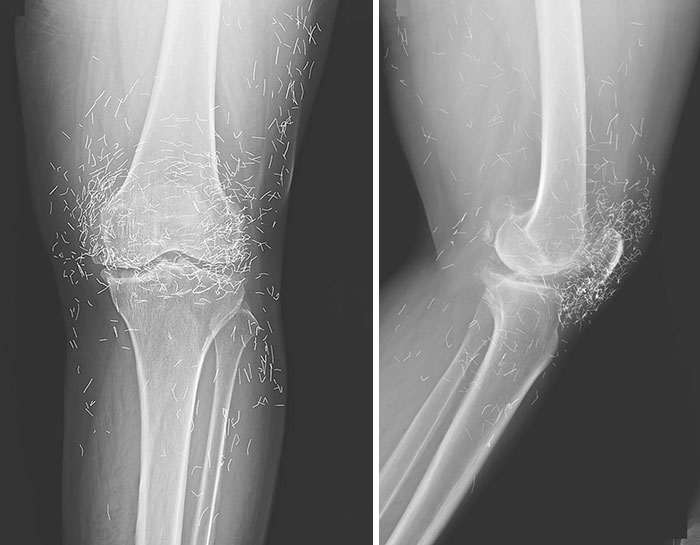

Запущенный ревматоидный артрит — приятного мало